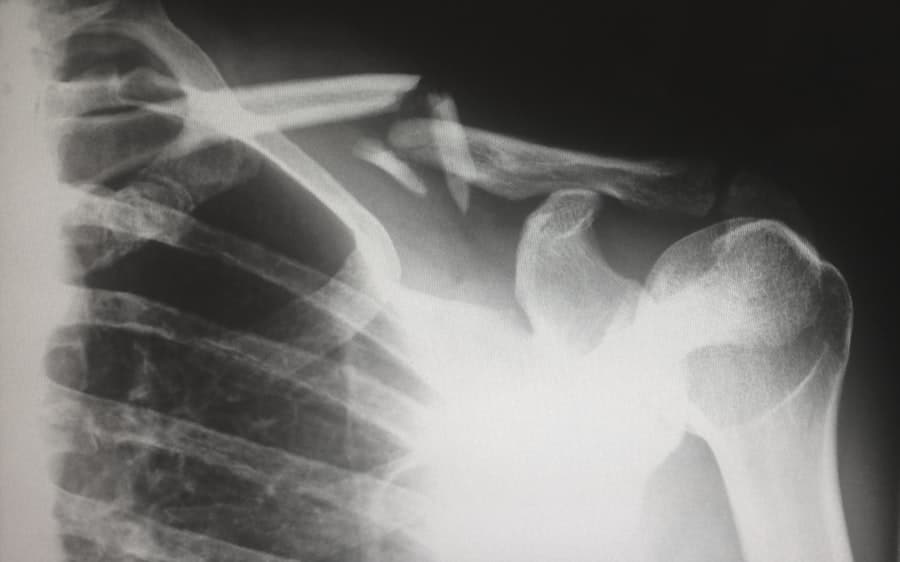

In some cases, imaging tests such as X-rays or MRIs may be necessary to visualize the structures within our lower back. These tests can help identify issues such as herniated discs, fractures, or signs of arthritis. By accurately diagnosing the underlying cause of our pain, we can work collaboratively with our healthcare provider to develop an effective treatment plan tailored to our specific needs.